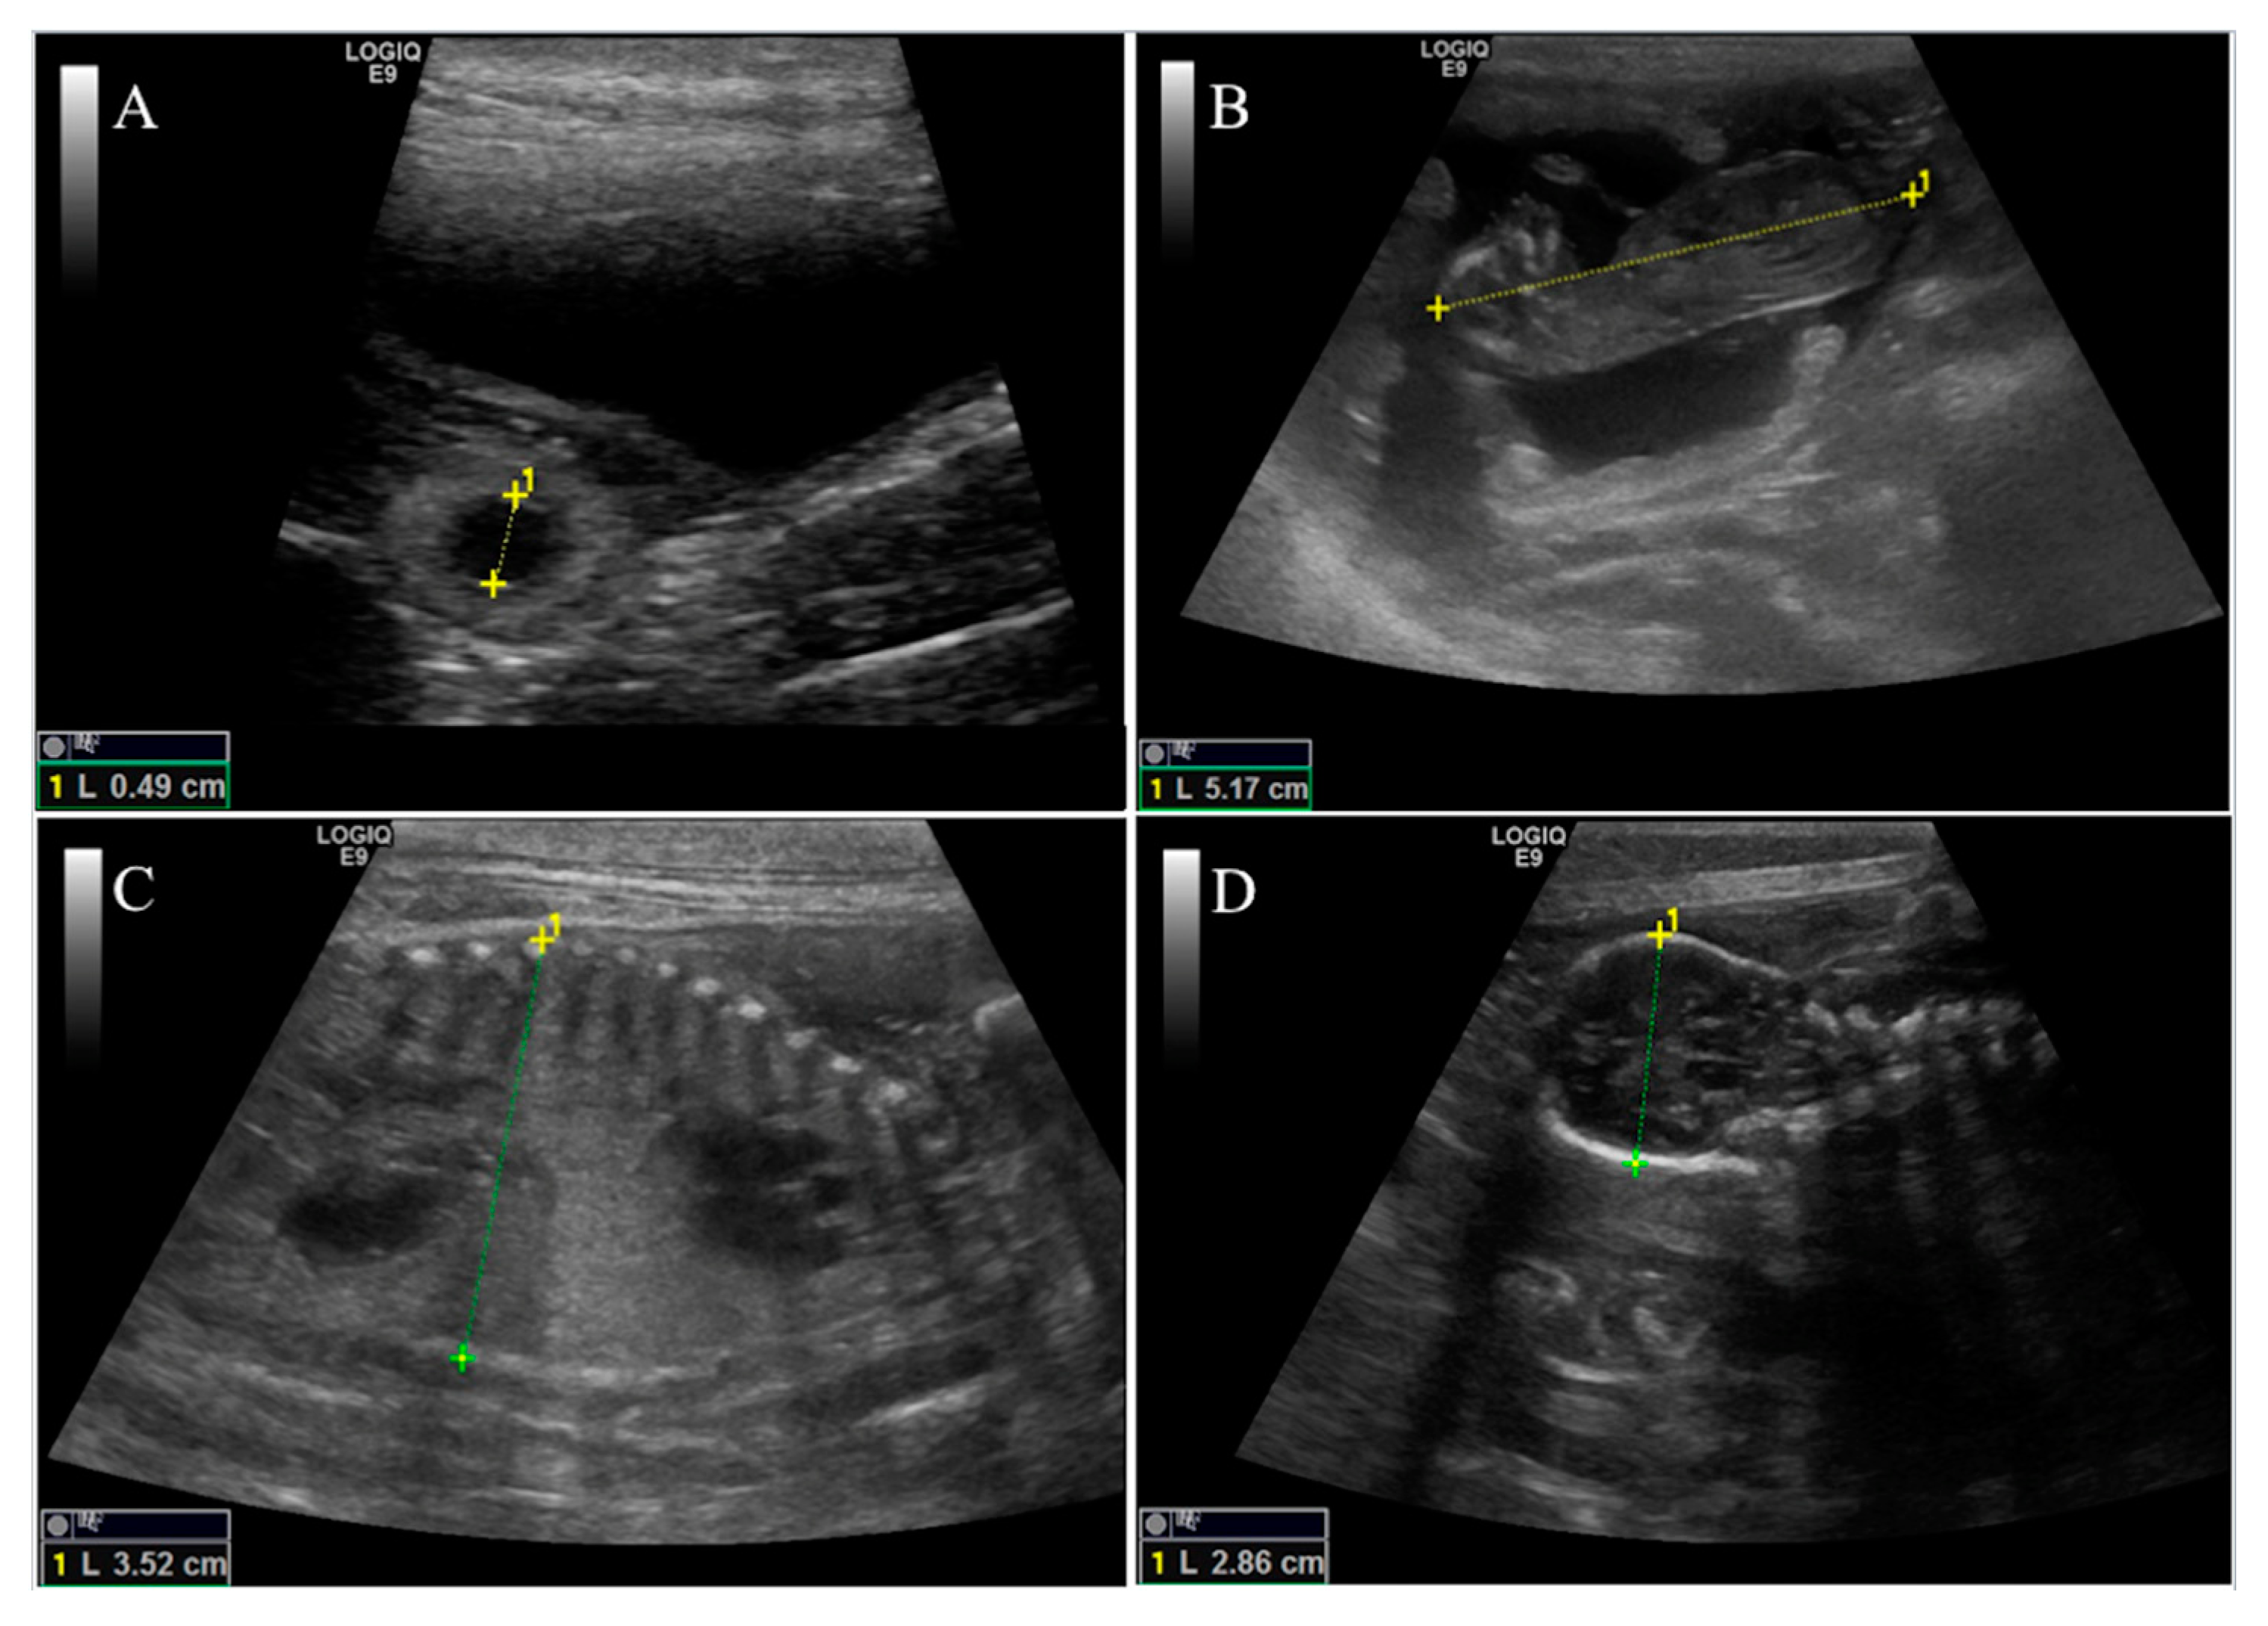

2.4. Ultrasound Scanning

- Inner chorionic cavity diameter—EX group showed higher values than CTR one and, in particular, on the 23rd day the difference was significant (1.30 vs. 0.80 cm; p < 0.05). Regarding size, the larger bitches showed higher values with a significant difference on the 23rd day (1.27 vs. 0.83 cm; p < 0.05) compared to bitches of medium size.

- Biparietal diameter—both effects (diet and size) did not affect this parameter, except for the 37th day when the diameter value of CTR group was significantly higher (1.36 vs. 1.13 cm, p < 0.05) than EX group one.

- The body diameter of the control group showed higher values than the experimental group even if the difference was significant only on the 41st day (1.91 vs. 1.61 cm, p < 0.05). Concerning size, until the 46th day, large bitches showed a higher diameter compared to bitches of medium size, while from the 46th day the values became similar.

- Crown-rump length—the control group showed a greater length during the first 50 days of gestation (50th: 10.74 vs. 9.75 cm, p < 0.05), afterward the values became overlapped. The embryos of large size bitches were always longer than those of medium-sized bitches.